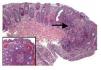

The patient, a 26-year-old woman, she was born in Mexico City without family history of IBD. She was referred to the hospital with a five months history of diarrhea with blood and blood watery stools. A colonoscopy and biopsy (Figure 1) confirmed ulcerative colitis (UC). Her symptoms were controlled after treatment. At the time of the diagnosis her marital status was single and she got married two years later. Currently she is under medical treatment for UC and she did not develop any complications related with UC. Her husband a 29 years old man born in Mexico City as well as his parents, but their grand parents came to Mexico from Spain. He was well for three years after he get married when he presented abdominal symptoms and the diagnosis of duodenal ulcer, tubulovillous colonic polyps, hepatic steatosis and hypercholesterolemia were made. One year later he developed diarrhea with blood. A colonoscopy and biopsy confirmed UC and no polyps (Figure 2) At the present time he is under treatment for UC and also for gastroesophageal reflux disease. He did not develop any complications related with UC.

Figure 2. In the biopsy of rectum are lymphoplasmocitary infiltrations diffuse and nodular with germinal centers (arrows) with distortion architectural pattern. In the crypts are diminutions in the mucous production (inset)